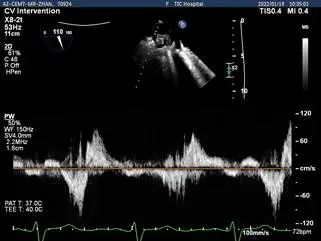

二尖瓣反流频谱呈全收缩期

肺静脉血流频谱呈收缩期反向

肺静脉血流频谱恢复正向